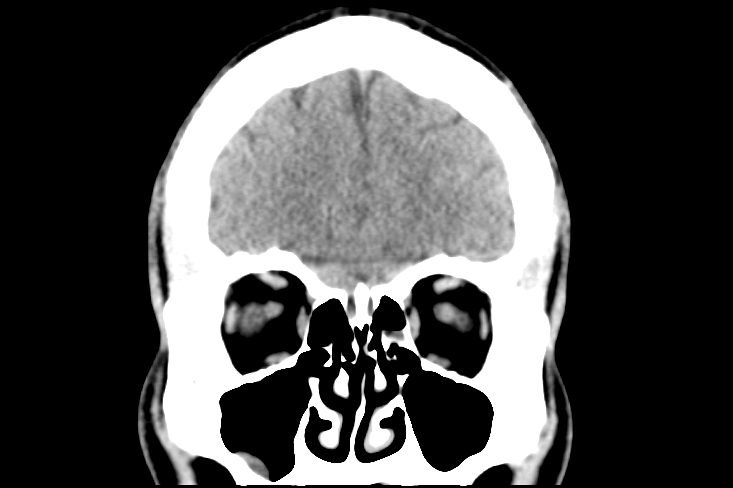

Intracranial Hemorrhages & Midline Shift

When trauma results in vascular rupture, timing and pressure are everything. We reconstruct the progression of intracranial bleeds to show the physical pressure exerted on brain tissue.

Hemorrhage Mapping

We visualize Epidural, Subdural, and Subarachnoid hemorrhages with patient-specific, Hounsfield-validated accuracy.

Mass Effect & Herniation

We use raw DICOM data to show the midline shift, providing a high-impact visual of life-threatening pressure and the displacement of vital structures.